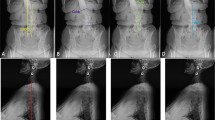

Different quantification methods are available to quantitatively characterize spine kinematics and posture. i) Spinal alignment angles in the frontal and sagittal planes are quantified in static conditions by means of imaging techniques [15], such as X-rays, CT or MRI scans [9, 15, 16]. These angles are commonly used in clinical practice to support diagnosis, surgical planning, and pre- and post-intervention assessment [9], but do not provide any characterization of spine function in dynamic conditions [16]. Static measurements are also affected by the limited repeatability of the measurements [15] with up to 20% change in lumbar lordosis values in subjects inter-session [17]. Additionally, depending on the spine pathology, imaging techniques are highly affected by lower levels of sensitivity, specificity and an increased rate of false positives with MRI being the most specific and sensitive test for LBP [18]. ii) Intervertebral 3D kinematics can be quantified using video-fluoroscopy [15, 16].This technique is highly accurate, detecting intervertebral ROM with a measurement error varying between 0.32° and 0.52° in the coronal and sagittal plane, respectively [19], but it is not exploited in clinical practice due to the small imaging volume preventing the analysis of spine segments, and due to the critical ionizing radiations exposure [20]. iii) Spine 3D angles can be quantified non-invasively using stereophotogrammetric motion analysis [21] without field of view limitations, allowing also for the assessment during daily living activities [22, 23], but can potentially be affected by significant experimental errors [24]. An overview of stereophotogrammetric motion analysis of the spine can be seen in Fig. 1.

Most studies used clusters of single markers for their setups, only 7 studies used marker triads to define spine segments [38, 53, 55, 68, 72, 83, 88]. The spinous processes of C7, T3, T6, T12, L1, L3 and L5 were the most widely used. All studies reported marker positioning by palpation of the anatomical landmark surface. Two studies positioned markers following the curvature of the spine, at the points of most thoracic kyphosis and lumbar lordosis [23, 64]. Information on the time needed to position the markers was not reported by any of the studies.